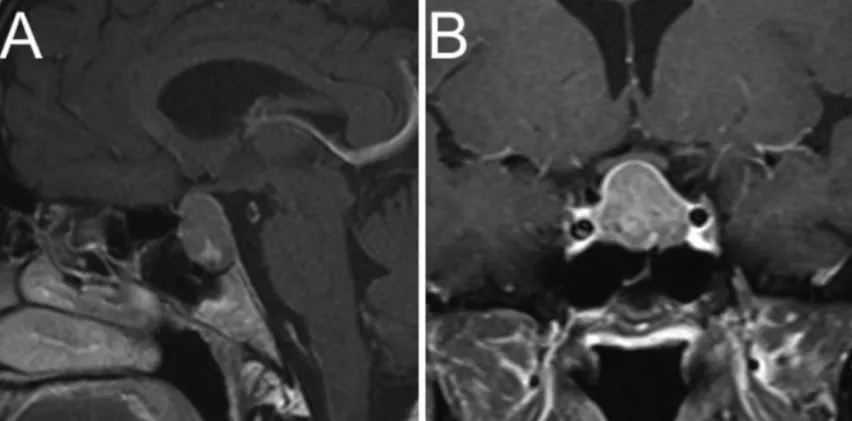

这是一例鞍上-鞍旁型大腺瘤

A、B:术前影像。